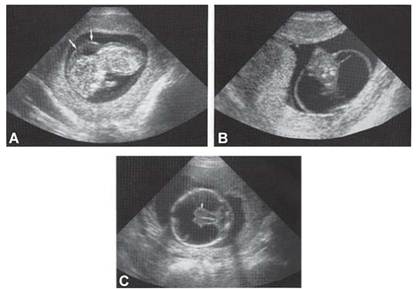

Many chromosomal defects have some ultrasound markers, and usually are called as soft markers (Fig. 1 and Table.3). Once such markers are observed, amniocentesis or fetal blood sampling should be considered for confirmation of a chromosomal syndrome.

Figs.1A to C: Some ultrasound markers of chromosomal disease (A) Nuchal translucency in trisomy 21,45X, (B) cystic hygroma in 45X, (C) holoprosencephaly

Table 3: Major chromosomal syndromes identifiable by ultrasound